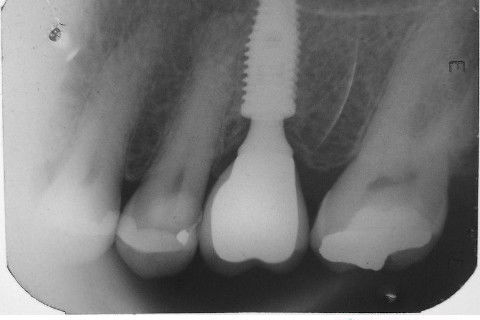

Instalação de um implante em região do 26. Utilizamos um implante cone morse Alvim Neodent 4.3 X 11,5. Foi uma cirurgia muito rápída e minimamente traumática, sem retalho e sutura.